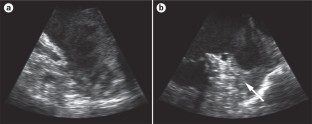

LAA flow stasis (or spontaneous echocardiographic contrast; SEC) is a pattern of blood flow (echogenicity) attributed to ultrasonic backscatter from blood cell aggregates that form under low shear conditions

SEC is formed through protein-mediated (particularly fibrinogen) red cell aggregation promoting red cell rouleaux formation, and is the cardiac factor most-strongly associated with LAA thrombus formation

Beppu, S. et al. Smoke-like echo in the left atrial cavity in mitral valve disease: its features and significance. J. Am. Coll. Cardiol. 6, 744–749 (1985).

Klein, A. L. et al. Integrated backscatter for quantification of left atrial spontaneous echo contrast. J. Am. Coll. Cardiol. 28, 222–231 (1996).